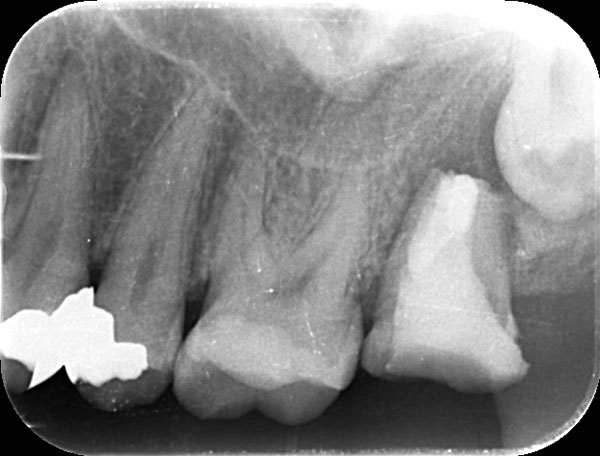

術前

術後

症例について

主訴:

歯茎が腫れたので診てほしい

治療内容:

感染や炎症を起こした歯の神経を取り除き、根の中を清掃・消毒したうえで再感染を防ぐ治療です。

治療期間:60分 1回

費用:初回根管治療 132,000円(税込)/ 支台築造 16,500円(税込)

治療に関わるリスクまたは副作用:

症状が改善しない場合や、再治療、外科的歯内療法が必要になることがあります。